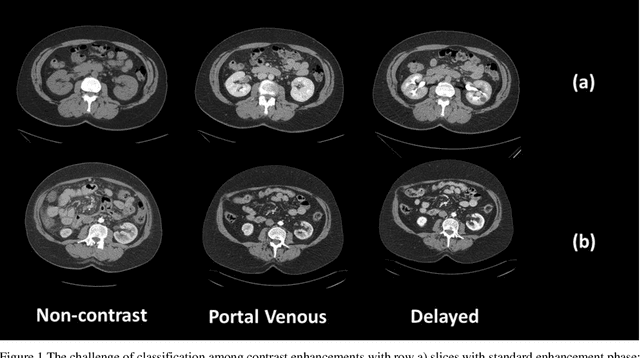

Abstract:Dynamic contrast enhanced computed tomography (CT) is an imaging technique that provides critical information on the relationship of vascular structure and dynamics in the context of underlying anatomy. A key challenge for image processing with contrast enhanced CT is that phase discrepancies are latent in different tissues due to contrast protocols, vascular dynamics, and metabolism variance. Previous studies with deep learning frameworks have been proposed for classifying contrast enhancement with networks inspired by computer vision. Here, we revisit the challenge in the context of whole abdomen contrast enhanced CTs. To capture and compensate for the complex contrast changes, we propose a novel discriminator in the form of a multi-domain disentangled representation learning network. The goal of this network is to learn an intermediate representation that separates contrast enhancement from anatomy and enables classification of images with varying contrast time. Briefly, our unpaired contrast disentangling GAN(CD-GAN) Discriminator follows the ResNet architecture to classify a CT scan from different enhancement phases. To evaluate the approach, we trained the enhancement phase classifier on 21060 slices from two clinical cohorts of 230 subjects. Testing was performed on 9100 slices from 30 independent subjects who had been imaged with CT scans from all contrast phases. Performance was quantified in terms of the multi-class normalized confusion matrix. The proposed network significantly improved correspondence over baseline UNet, ResNet50 and StarGAN performance of accuracy scores 0.54. 0.55, 0.62 and 0.91, respectively. The proposed discriminator from the disentangled network presents a promising technique that may allow deeper modeling of dynamic imaging against patient specific anatomies.